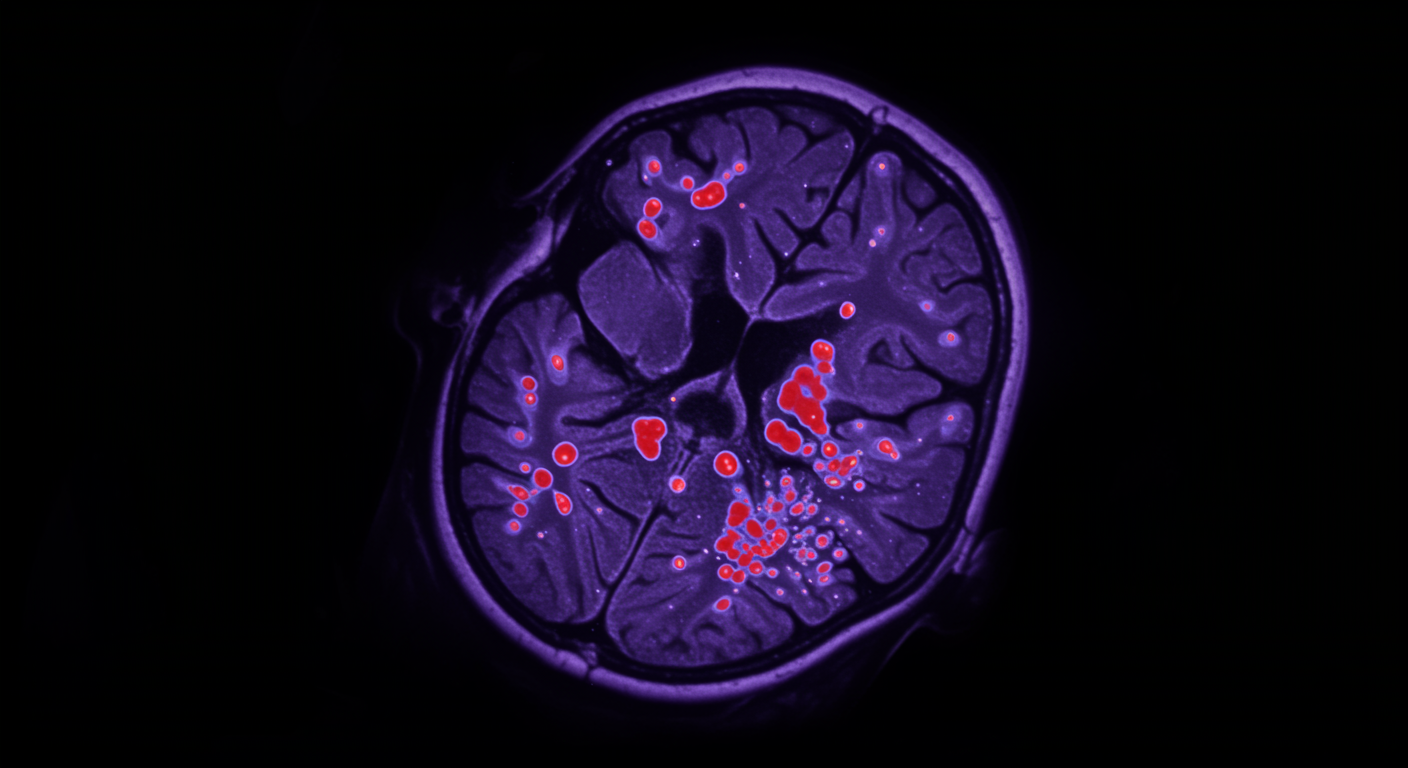

Sawtooth waves are distinctive brain wave patterns that occur during REM sleep, characterized by their sharp, serrated appearance on EEG recordings. This advanced neuroimaging research reveals that these waves are associated with widespread brain activation across multiple regions, providing crucial insights into how the brain generates dreams and processes memories during REM sleep. The waves appear to coordinate neural activity across distant brain regions, facilitating the complex cognitive processes that occur during our most vivid dreaming periods.